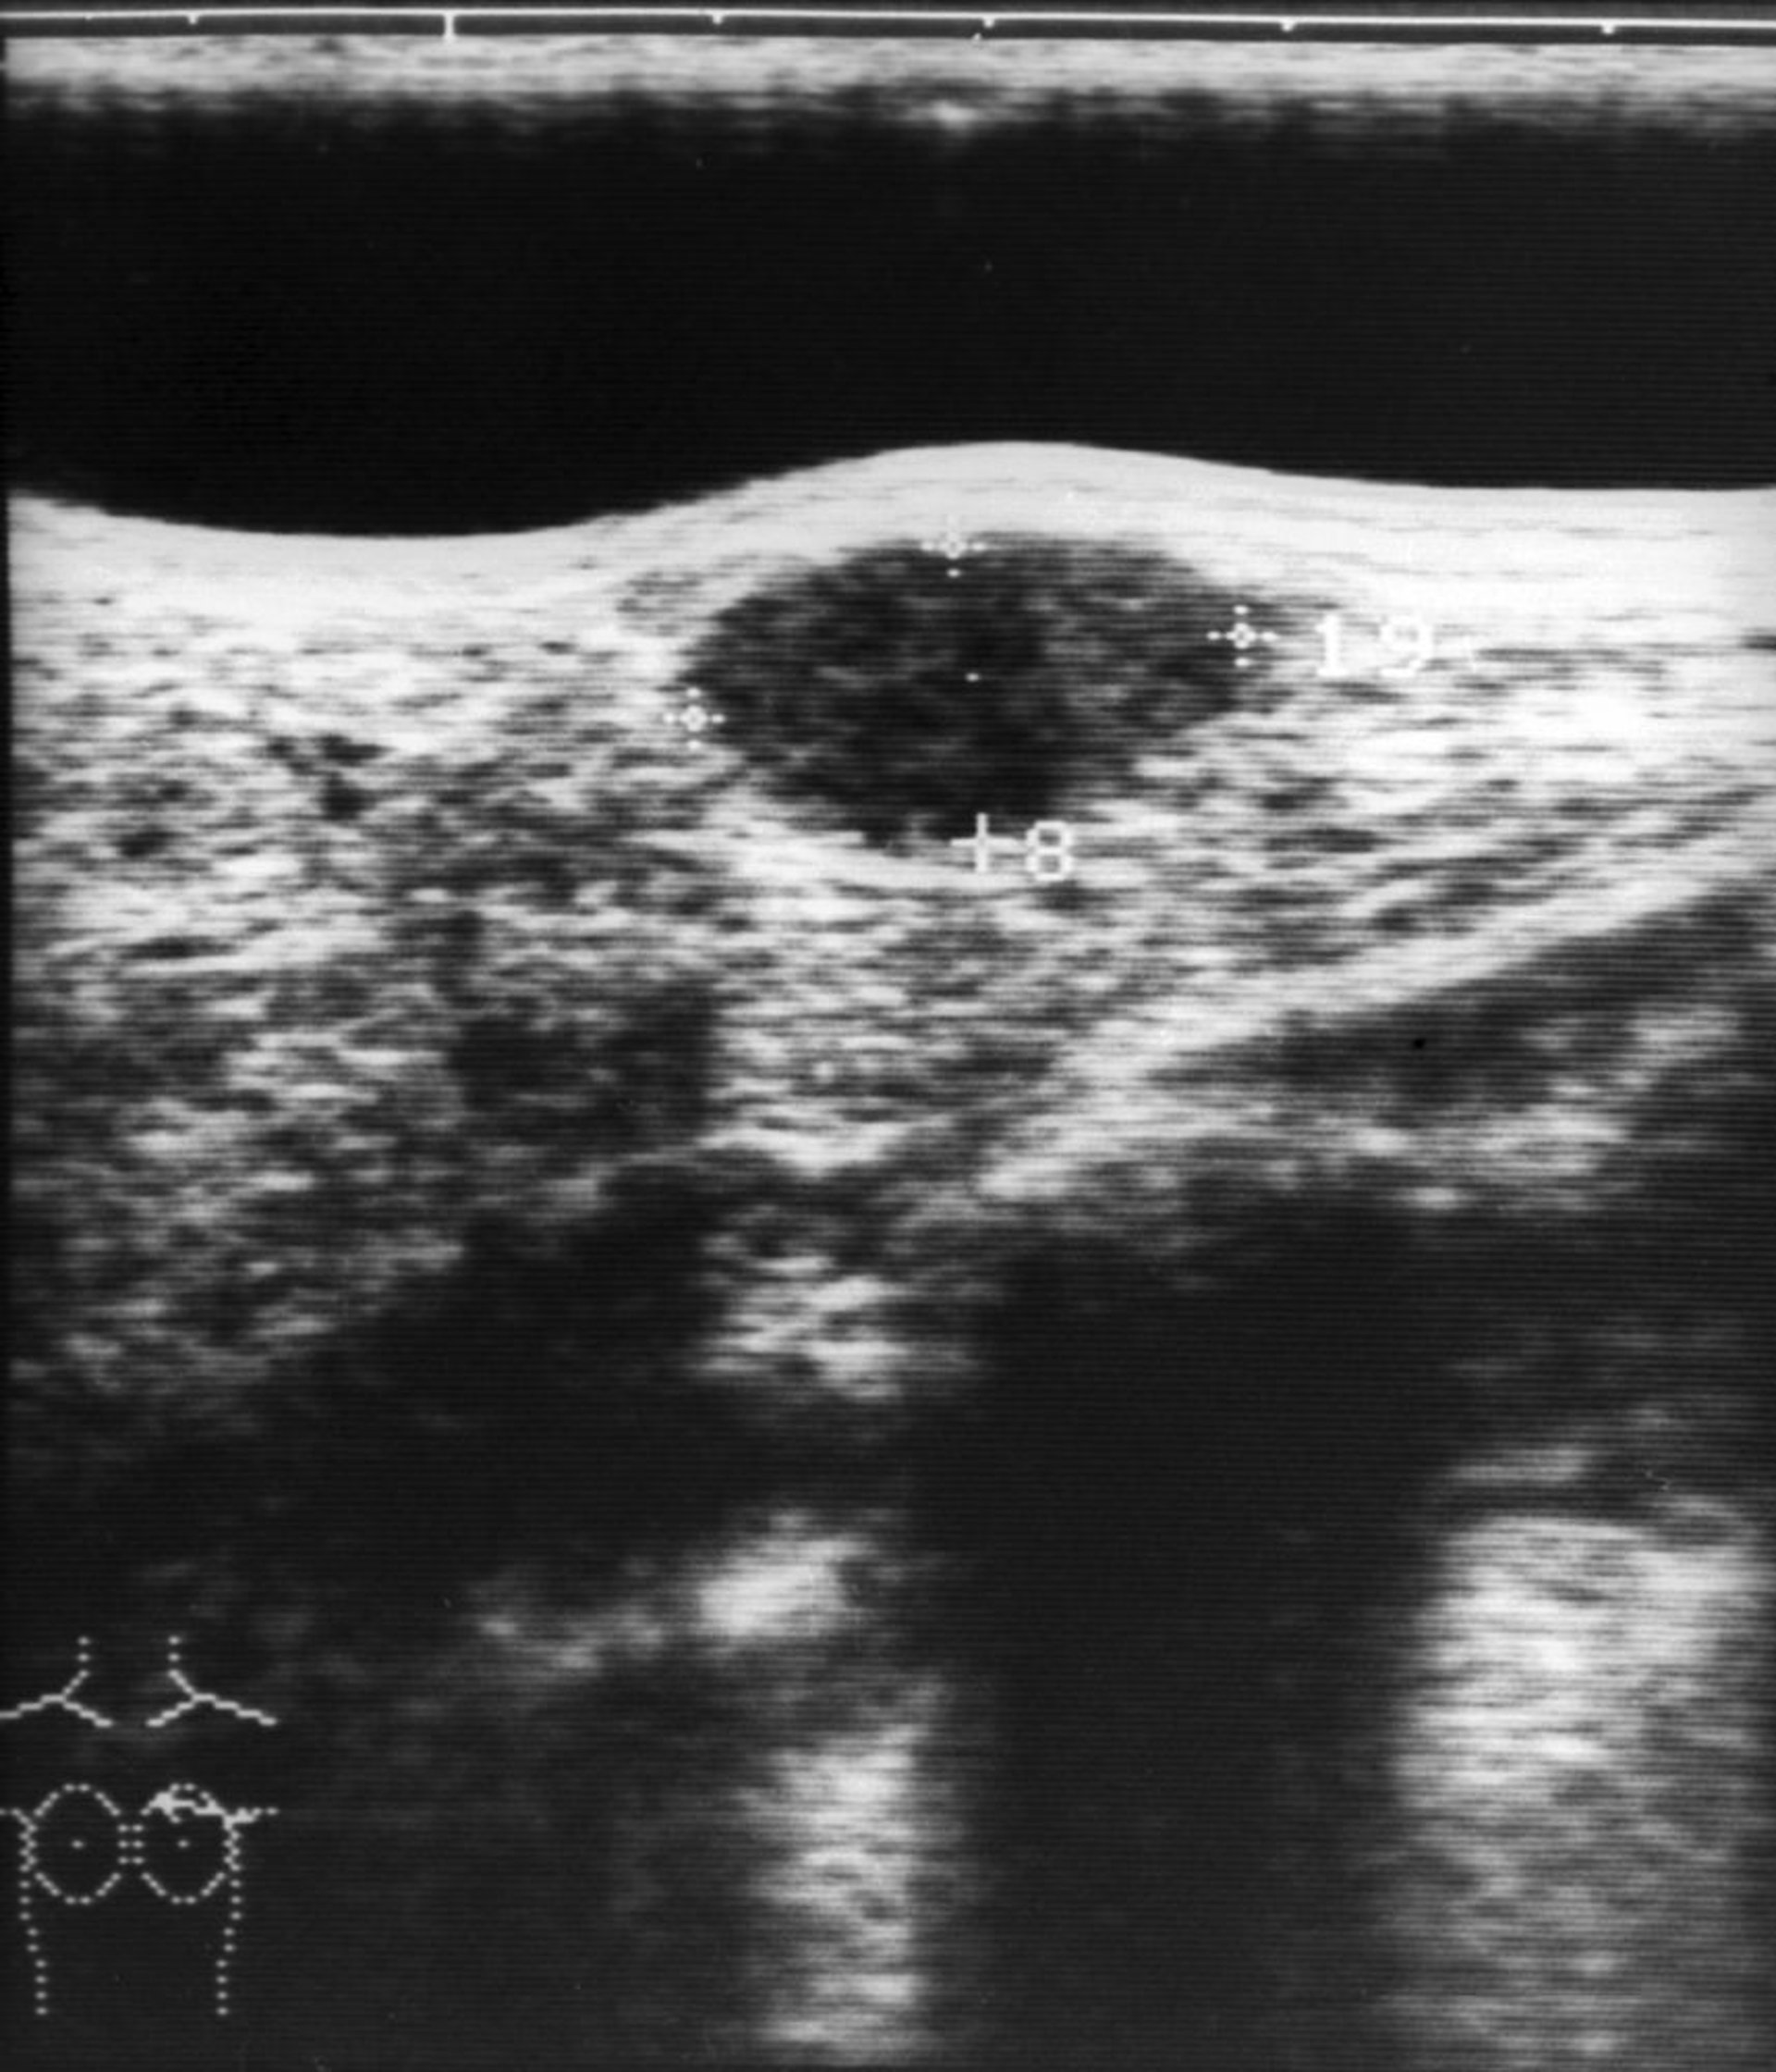

Hình ảnh này cho thấy siêu âm của một khối u tuyến xơ ở vú (cấu trúc giảm âm hình bầu dục ở trung tâm phía trên của hình ảnh).